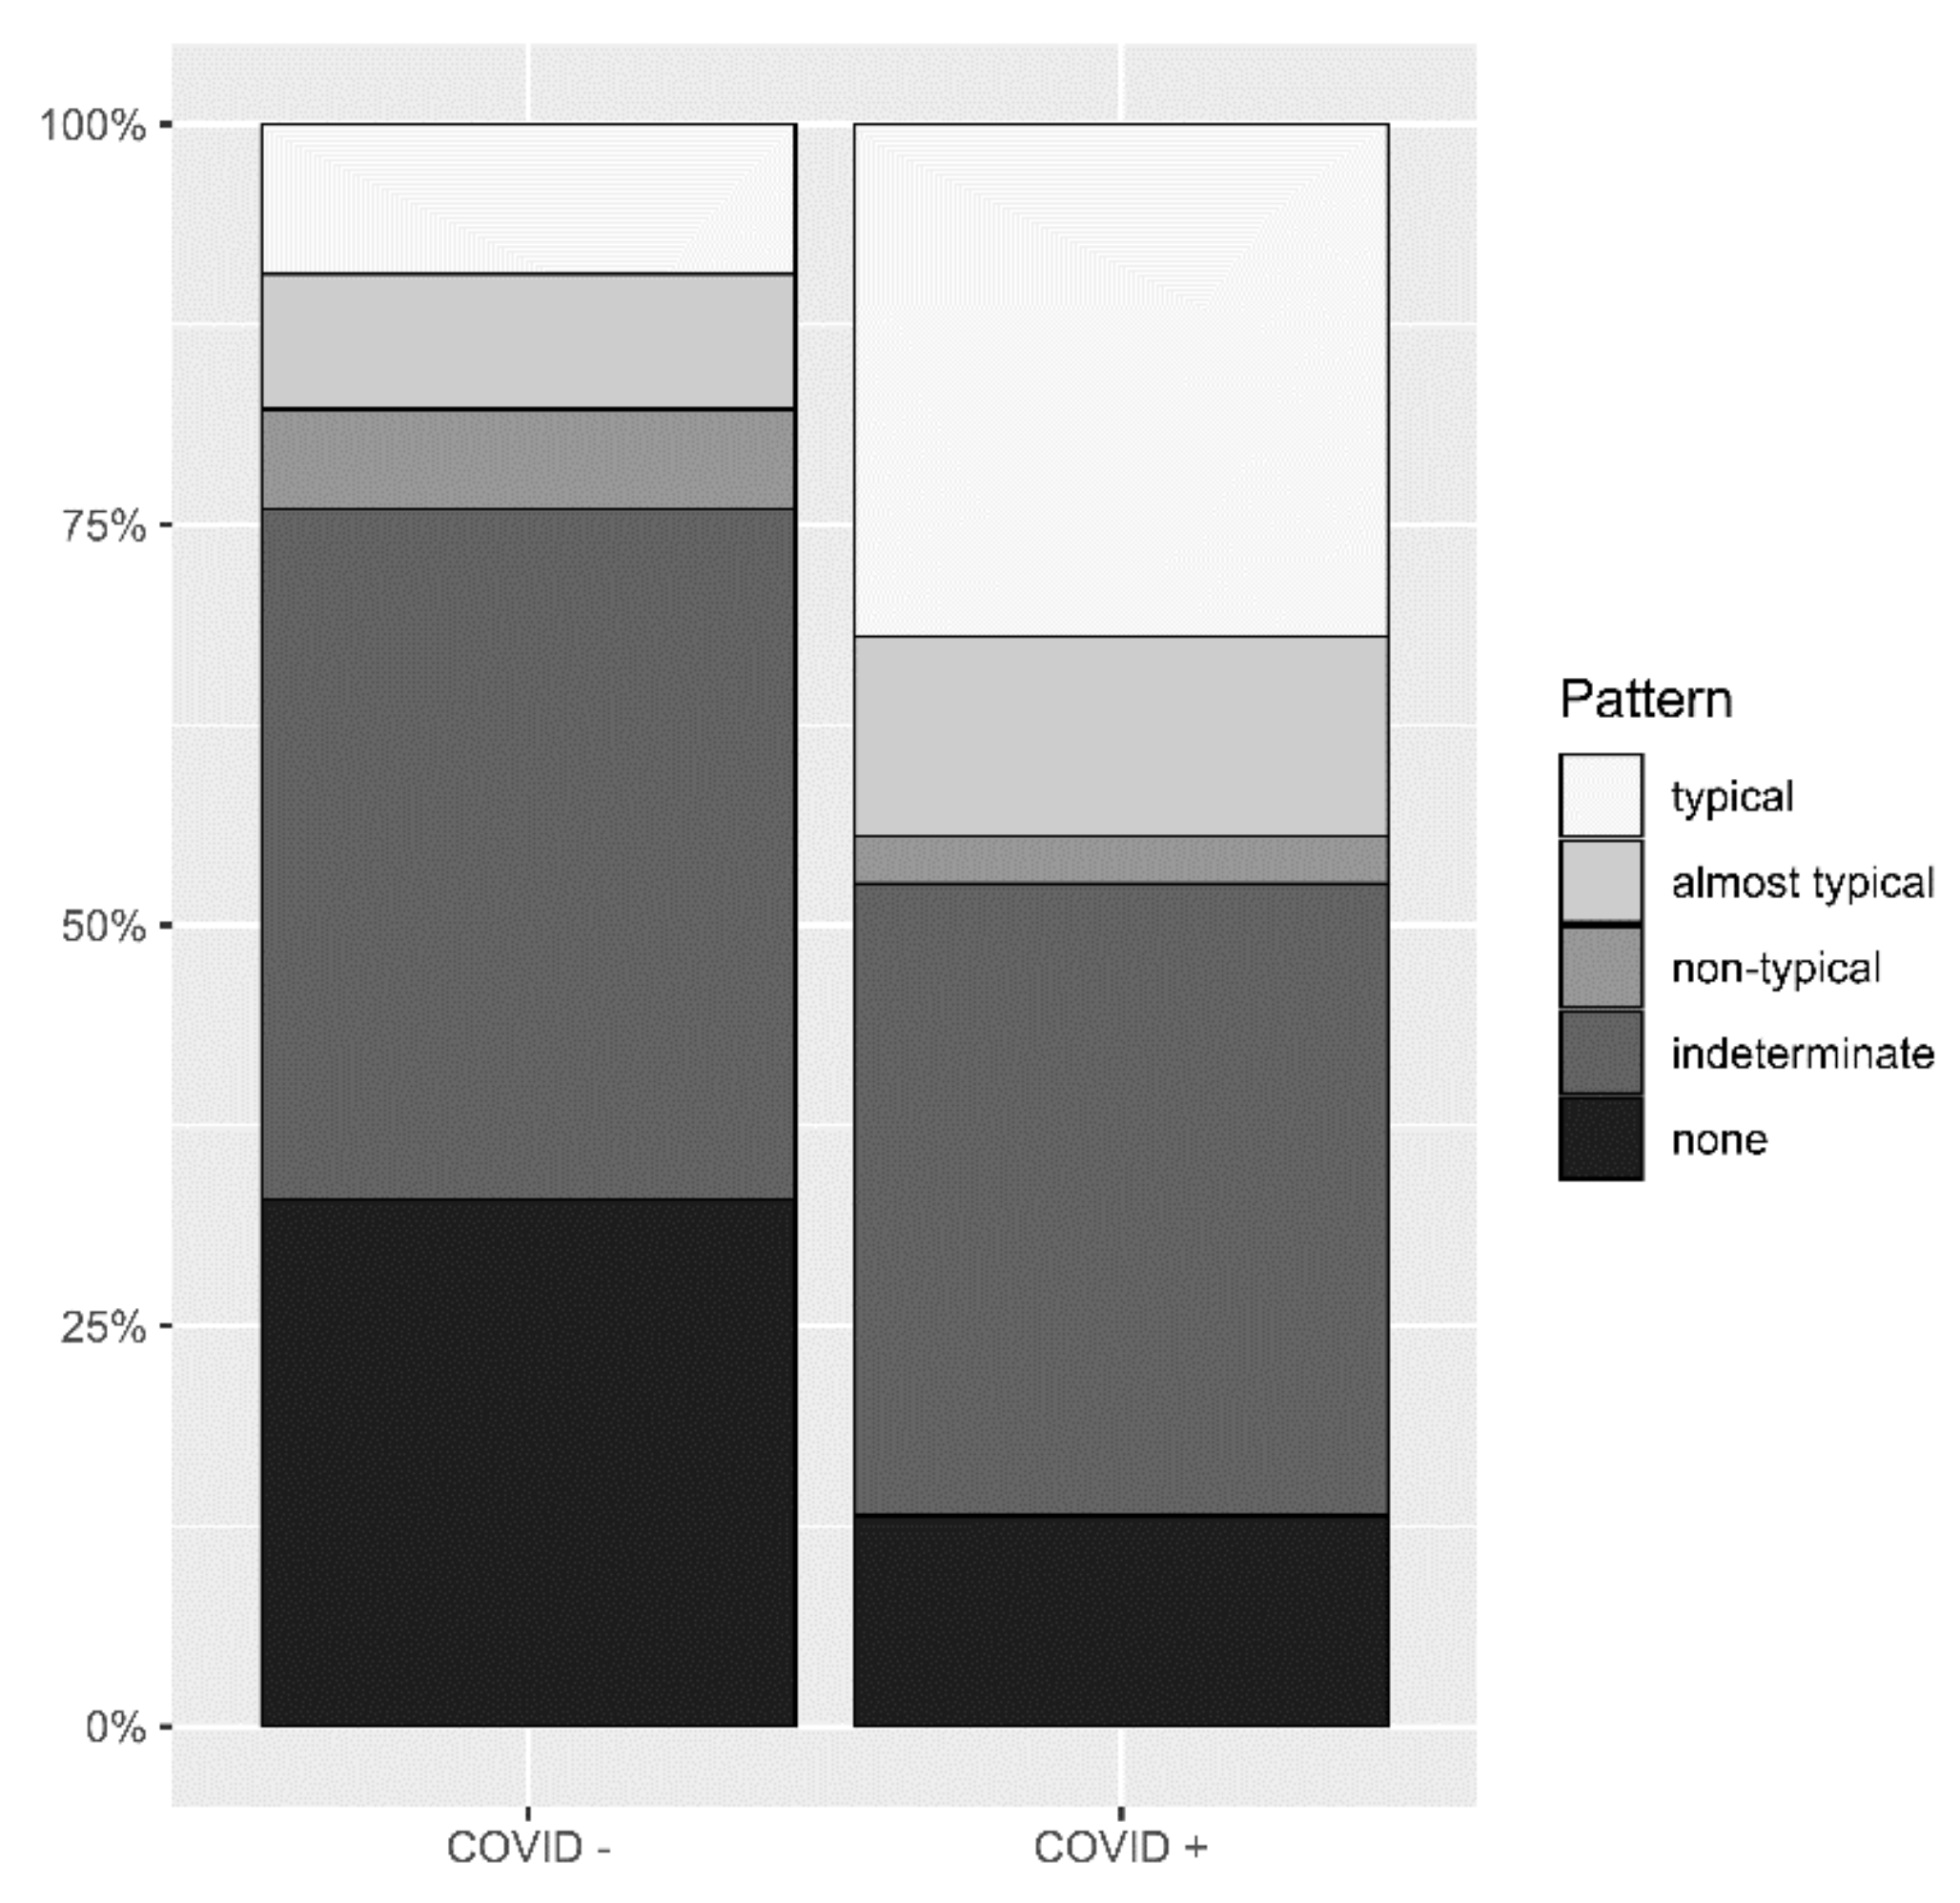

3.2. Identification of Pneumonia by Radiologists

3.3. AI-Based Diagnostic Performance